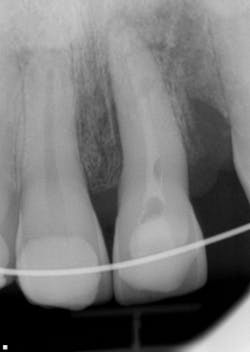

Clinical and radiographic assessment revealed the following (figure 1):

- Complete loss of tooth No. 10 (the patient did not know where the tooth went upon impact).

- Significant swelling in the maxillary and mandibular labial areas with bruising and slight lacerations on the lip and tongue, which were caused when the lower teeth impacted the maxillary teeth with the tongue in between.

- A significant lingual laceration of papilla interproximal to Nos. 8 and 9 with possible involvement of the incisive nerve. Bone exposure was evident.

- Partially avulsed and lingually displaced tooth No. 9 with Class 4 mobility. There was tissue retention only (very light and unstable).

- All other teeth mesial and distal to No. 9 appeared secure.

- Radiographic assessment revealed a horizontal fracture of the alveolar interproximal bone between Nos. 9 and 10 at the apical one-third area. Tooth No. 9 was separated from the alveolar bone with partial avulsion. It was unclear whether the root tip was fractured.

- The patient was unable to bite down due to the mobility and lingual position of No. 9.

Figure 1